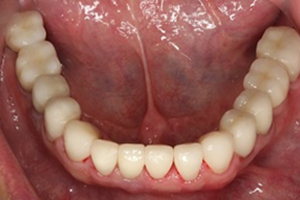

治療後

人工植牙與全口治療